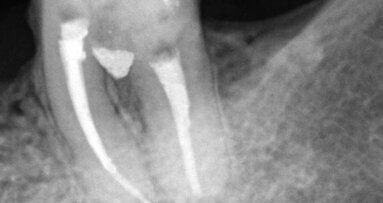

Fig 1: In the first lower molar an X-ray can often show a bone loss between roots and diagnosis is easier than other teeth.

Fig 1: The MTA sandwich technique is the author’s personally recommended repair method for this kind of perforation and it has been well described by Fabio Gorni in this article.